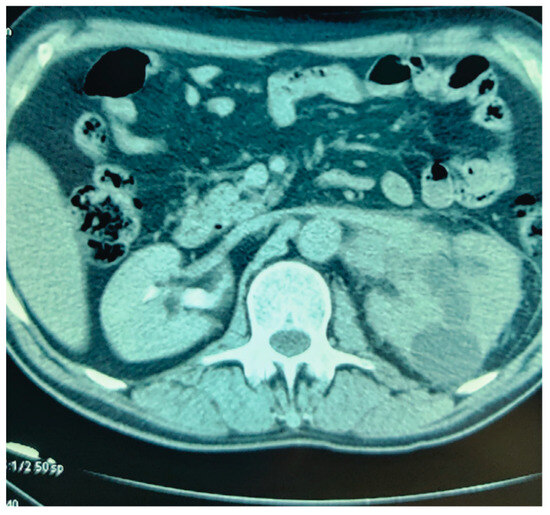

Our 65-year-old patient reported repeated renal colic, with air emission during urination, and presented with a pyelo-colic fistula (Figure 1 and Figure 2). Radical treatment was carried out. The anatomo-pathological analysis showed a chronic pyelonephretic kidney abscessed. with a destroyed kidney.

Figure 1.

Cross section of the left kidney Pyelocalycial dilation.